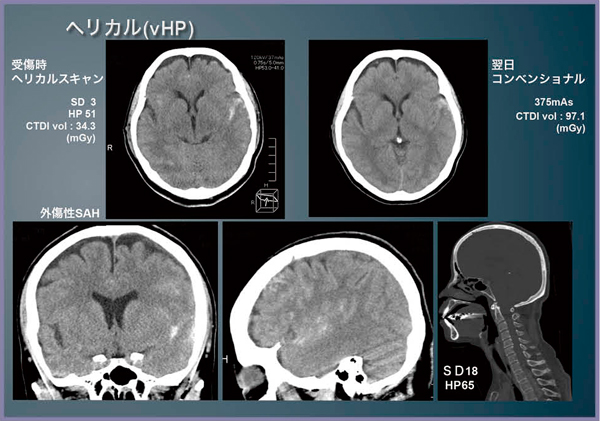

救急の頭部単純CTの撮影を,コンベンショナルで行うか,ヘリカルスキャンを選択するかについてはさまざまな見解があるが,当センターでは基本的にコンベンショナルスキャンを行っている。しかし,最近では,顔面外傷や頭部外傷がある場合には,vHPを使った頭頸部のヘリカルスキャンを始めている。プロトコルは,頭部をSD3,HP51,頸部をSD18,HP65で撮影し,AIDR 3DはWeakを使用する(図6)。

頭頸部でvHPによるヘリカルスキャンを行った症例を提示する(図7)。バイクの単独事故で搬入された患者で,搬入時,見当識のあるJCS2で耳出血があった。搬入時のヘリカルCT(図7左上)と,翌日に撮影したコンベンショナルCT(図7右上)では,画質だけを比較するとコンベンショナルCTが優れているが,外傷患者の搬入時検査においてはヘリカルスキャンでも十分な診断能力があると考える。外傷CTの読影方法である“FACT(Focused Assessment with CT for Trauma)”においても,頭部の評価のポイントは緊急開頭が必要な血腫などの有無であり,そのためにはモーションアーチファクトに強く,多断面から総合的に判断できるヘリカルスキャンが有益と考える。